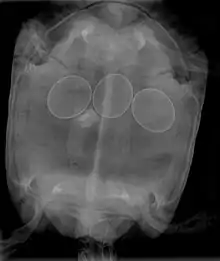

Ce symptôme est particulièrement surveillé par les aviculteurs et par les éleveurs d'oiseaux ou de tortues de compagnie. C'est une manifestation subjective de nombreuses maladies, de carences ou de malformation d'œufs. Les femelles présentent un abdomen gonflé et deviennent amorphes et anorexiques.

Tortue

L'ocytocine et le gluconate de calcium sont utilisés[2].